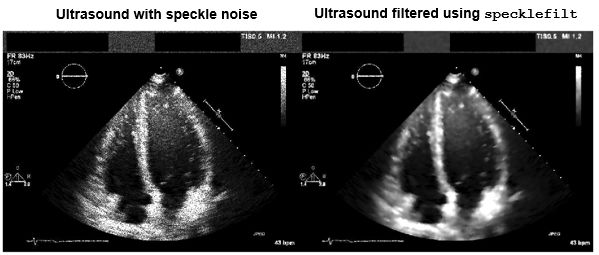

Side-by-side comparison of original ultrasound and ultrasound with speckle noise filtered out.

Reducing speckle noise in an ultrasound image using the specklefilt function in MATLAB. (See code example.)